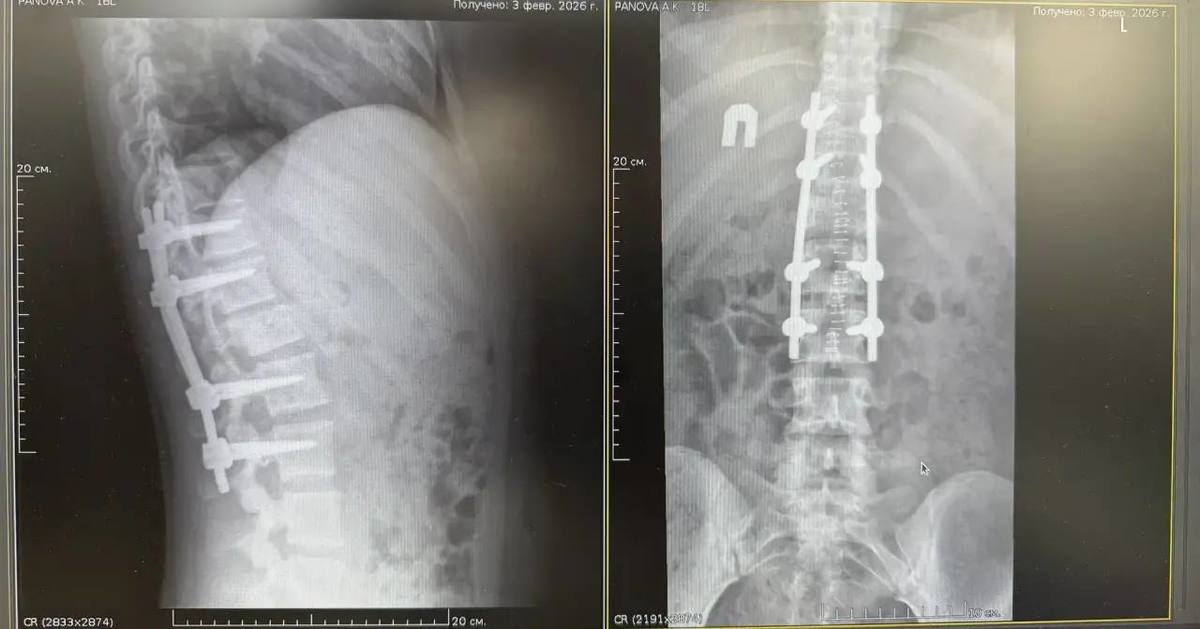

В Тысячекоечную больницу 19 января из Арсеньева была доставлена 18-летняя девушка с диагнозом «компрессионный перелом тела позвонка со стенозом позвоночного канала». Травма привела к сдавливанию спинного мозга, что вызвало неврологический дефицит (парез ног) и нарушение функций тазовых органов. Нейрохирурги провели сложное 4-часовое вмешательство и в итоге сделали всё, чтобы травма осталась только в прошлом. Сейчас девушка выписана на амбулаторное лечение.